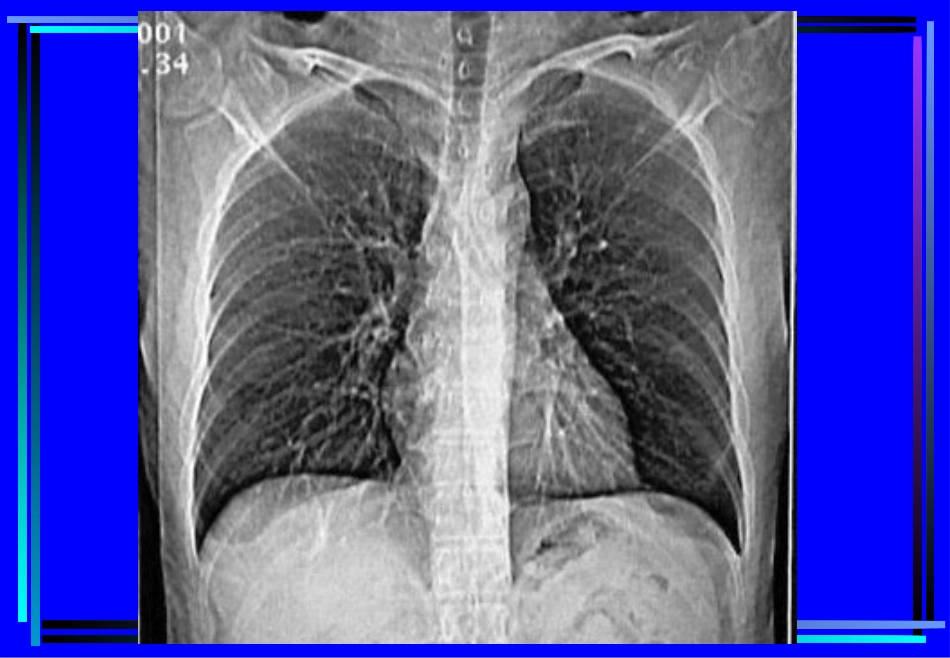

胸部CT诊断第一节胸部CT检查一、胸部CT扫描方法(一)普通扫描(平扫plainCTscan)(二)增强扫描(contrastenhancement,CE)1.注药方法团注法(bolusinjection)静滴法2.扫描程序静态CT扫描动态CT扫描(dynamicCTscan)(三)特殊扫描1.薄层扫描2.高分辨率CT扫描(HighresolutionCT,HRCT)3.CT血管造影(CTangiography,CTA)4.心电门控扫描二、CT对胸部疾病的诊断价值与限度(一)诊断价值1.肺部小病灶与早期病变2.咯血查因3.肺不张、肺实变4.肺肿瘤分期5.肺弥漫性病变6.肺气肿的诊断及功能评价7.肺血管性病变8.胸水查因(二)影响CT检出与诊断的因素(主要为常规CT)1.运动伪影2.部分容积效应3.层厚与层间距4.大量胸水5.一病多像,一像多病三、胸部正常CT解剖(一)窗技术1.纵隔窗:窗位30-60Hu,窗宽300-500Hu2.肺窗:窗位-700~-400Hu,窗宽1000-1500Hu(二)纵隔(mediastinum)(三)肺(lung)第二节肺部疾病的CT诊断一、先天性疾病1.肺隔离症(pulmonarysequestration)某一肺段和正常肺组织及气管和支气管树相互分离,无呼吸功能,血供来自主动脉系统,分叶内型和叶外型两类。CT表现:部位:两下肺、脊柱旁。形态:囊实性或囊性或实性,邻近肺野斑片状影。血供:体循环,病灶内血管异常。鉴别诊断:支气管源性囊肿、肺脓肿、先天性膈疝。2.支气管囊肿(bronchogeniccyst)为支气管的先天发育异常,根据组织学来源可分为支气管囊肿和支气管肺囊肿(pulmonarybronchogeniccyst)。CT表现:部位:纵隔与肺的任何部位,多见于气管隆突5cm范围内。形态:圆形、椭圆形、边缘锐利,壁菲薄。密度:均匀,可有出血和液气平,壁可强化。二、支气管扩张症(bronchiectasis)病因:先天性或后天性病理:肉眼观,支气管呈柱状、囊状、静脉曲张状或混合状扩张。镜下观,粘膜柱状上皮呈急、慢性炎性改变,伴弹力纤维、平滑肌和软骨的损害。CT表现:病变支气管壁增厚,管腔扩大,形态多样。1.柱状扩张:“双轨”征、“印戒”征。2.囊状扩张:葡萄串状、卷发样。3.曲张形扩张:粗细不均的囊柱状。4.混合型合并粘液栓时,腔内可见棒状或结节状软组织密度影,咳痰后可消失,同时可见肺野内出血,继发感染等征象。三、肺感染性病变1.支气管肺炎支气管肺炎(bronchopneumonia)或小叶性肺炎(lobularpneumonia)病理:小支气管壁充血、水肿、间质炎性细胞浸润,小叶渗出、实变、气肿或不张。CT表现:两肺中下野中内带,支气管血管束增粗,沿其分布小斑片影及边缘模糊的小结节影。2.大叶性肺炎大叶性肺炎(lobarpneumonia),炎症累及整个肺叶,或呈肺段分布。病理:充血期,毛细血管充血,肺泡内可有少量浆液性渗出。红色肝样变期,渗出液中含较多红细胞。灰色肝样变期,渗出液中含大量白细胞。消散期,渗出液溶解、吸收。CT表现:渗出期表现为磨玻璃样影;实变期呈叶、段的实变,可见空气支气管征,叶间裂可向外膨出;消散期则呈斑片状影。鉴别诊断:阻塞性肺炎,结核性大叶炎、肺肿瘤(腺癌、肺泡癌或淋巴瘤)。3.肺脓肿肺脓肿(lungabscess),由化脓性细菌引起的肺坏死性炎性病变,分急性和慢性肺脓肿。病理:细支气管阻塞,小血管炎性栓塞,肺组织坏死、液化,周围有纤维组织增生。CT表现:急性期:大片密实影,中心密度较低,空洞形成后,壁厚而模糊,内有液平;慢性期:洞壁清晰,内壁多不规整,增强扫描洞壁强化,支气管、肺血管于脓肿边缘截断。鉴别诊断:结核空洞、癌性空洞4.肺结核肺结核(pulmonarytuberculosis),由人型或牛型结核杆菌引起的肺部慢性传染病。病理:渗出-结核性肺泡炎,增殖-结核性结节肉芽肿。继发改变:干酪样坏死、液化、空洞、播散;纤维化、钙化。CT表现:Ⅰ型:原发性肺结核(primarytuberculosis)纵隔、肺门淋巴结增大,增强扫描多呈环形强化。肺内原发灶呈片影或段、叶的实变,内可见低密度坏死、空洞。可合并叶或段的不张。Ⅱ型:血行播散型肺结核(acutemiliarytuberculosisandchronicdisseminatedtuberculosis)急性血行播散型,CT表现为双肺广泛分布的1-2mm小点状阴影,密度均匀,边界清,分布均匀,与支气管走行无关,以HRCT显示为佳。亚急性或慢性血...